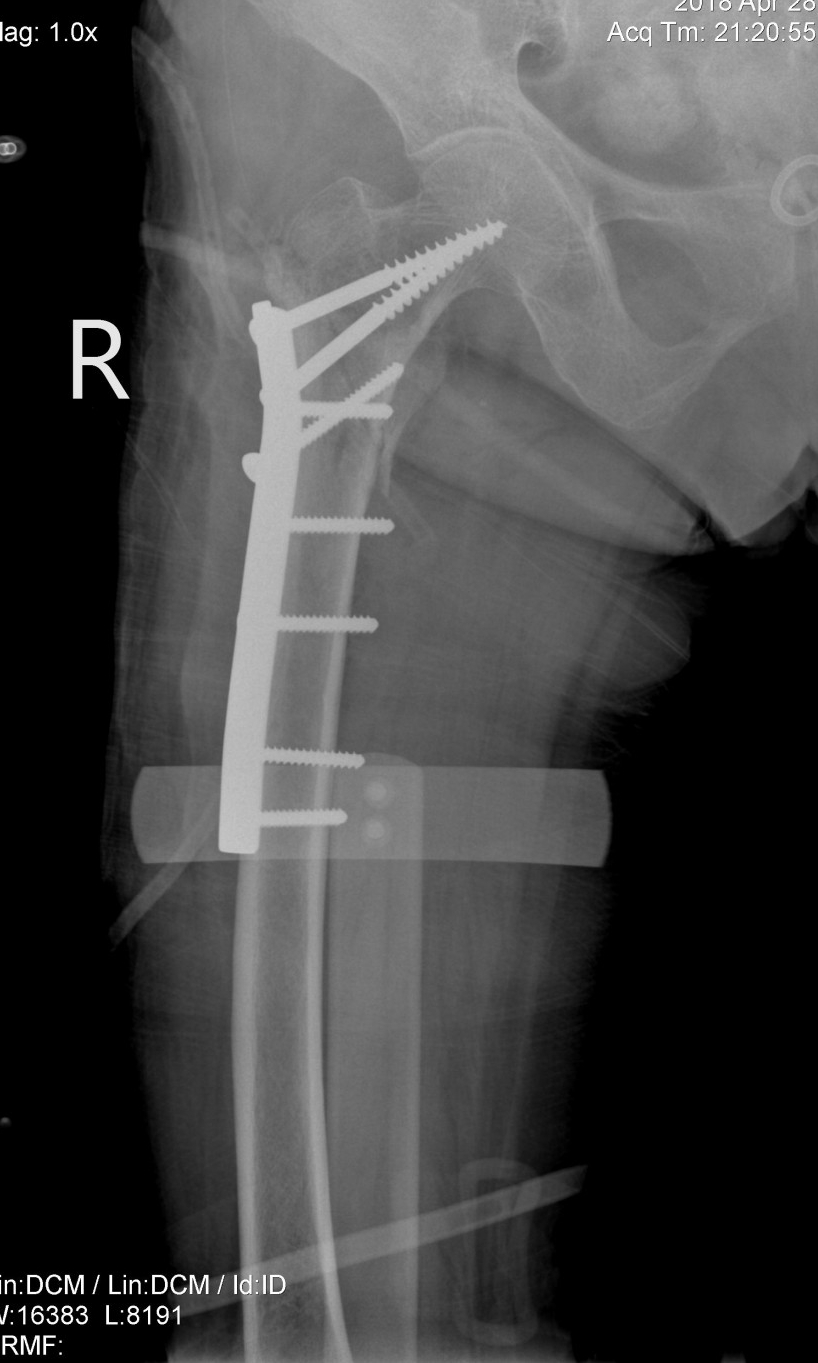

Qua cận lâm sàng Bác sỹ chẩn đoán bệnh nhân bị gãy liên mấu chuyển xương đùi phải.

Ngay lập tức hội chẩn Bệnh viện gồm các Bác sỹ khoa Hồi sức cấp cứu, khoa Ngoại, khoa Nội – Nhi – Đông y được tiến hành do chỉ định phẫu thuật cho cụ vô cùng khó khăn, cụ có tiền sử mắc nhiều bệnh nội khoa mạn tính bên cạnh đó tuổi cụ đã cao khi phẫu thuật cần có đội ngũ chuyên môn giỏi và phối hợp nhịp nhàng từ khâu nhỏ nhất. Cuộc hội chẩn quyết định phương án phẫu thuật kết hợp xương đùi phải cùng ekip phẫu thuật là các Bác sỹ chuyên khoa xương khớp Bệnh viện đa khoa Hùng Vương.

Ca phẫu thuật được tính toán cẩn thận, sự chuẩn bị trước mổ chu đáo, cùng với kỹ thuật gây tê tủy sống và giảm đau sau mổ đã giảm bớt nguy cơ trong và sau mổ, giúp cho ca phẫu thuật thành công.

Sau phẫu thuật bệnh nhân tỉnh táo, niêm mạc hồng. Hiện bệnh nhân đang được theo dõi tích cực tại khoa Hồi sức cấp cứu Bệnh viện đa khoa Hùng Vương. Do bệnh nhân tuổi cao xương đã loãng nên phải kiêng và vận động ít sau hơn 1 tháng mới có thể tập các bài phục hồi chức năng theo hướng dẫn của bác sĩ.